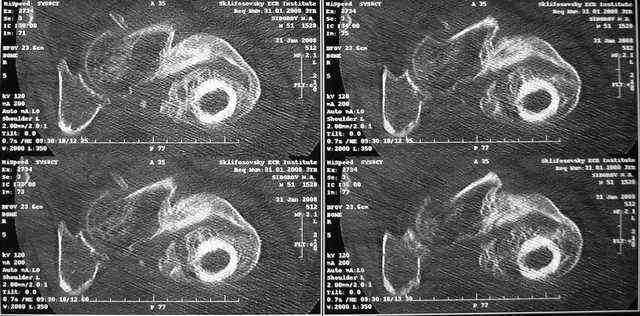

Рентгенологическая картина — рис. 2. При КТ: признаков аваскулярного

некроза головки бедренной кости нет, головка находится в ретроверсии

(рис. 3).